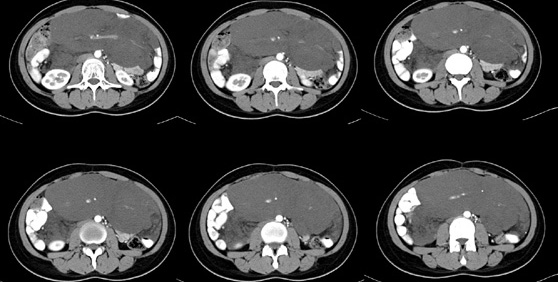

女性,28岁,停经3月,腹部膨隆1月,产前检查发现腹部占位

{肿块中心ct值27hu,增强后,动脉期、门脉期均无明显强化)

患者手术病理:腹腔囊性淋巴管瘤,象这样充满整个腹腔的的确很少见